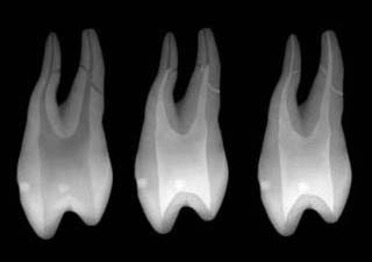

The convenient, "all-in-one" Endo Access Kit provides an economy of burs to initiate, progressively expand, and completely finish any access preparation.